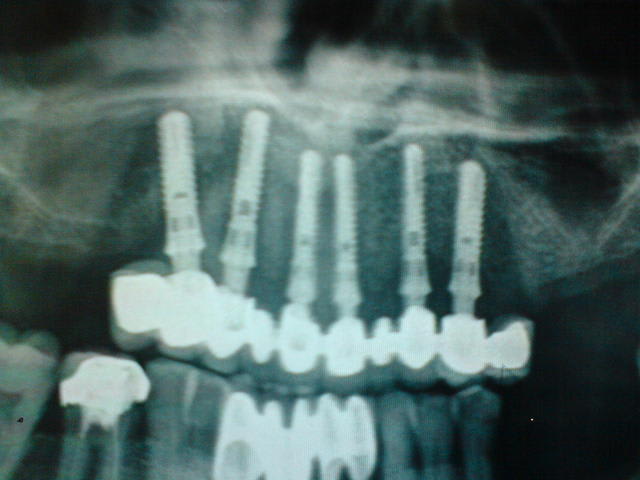

Patient de 50 ans, greffé des reins sous dialyse réguilère, d'origine egyptienne.

Il vient me voir avec le souci suivant: il s'est fait posé six à huit implants maxillaires (j'attend la pano pour les denombrer) il y a 4 mois en egyptes avec mise en charge 6 jours plus tard d'un bridge céramique 15 a 25 (avec 15 25 en extension).

En bouche, bah ca bouge, et a la radio a priori les implants ne sont pas ostéointégrés.

ce sont pas des straumann, ils ont l'air autotaraudant....

apres depose du travail (en fait 4 sont venus en tirant sur le bridge )je lui ai reposé la question....il a confirmé le prix et m'a dit que pour sa soeur c'etait 580 mais elle en a dix avec bridge qui tient depuis un an...j'essaierai de prendre une photo du travail opur le poster.

Sinon, chirrugicalement, bah il a peu ou plus de table osseuse , et au niveau premolaire je crois que la membrane sinusienne sera acollée directement a la muqueeuse alveolaire....quel bonheur.

Y a un implant que j'ai pas réussi a retirer donc ca fait quand meme un pourcentage de reussite convenable au prix non? ok je rigolais.

bon j'ai juste pris les photos avec mon telephone car j'en ai marre d'oublier le vrai appareil. Vous connaissez cette marque?

on dirait des straumann...

c'est pas straumann, y a pas de rainure de côté

Pour les implants je sais toujours pas la marque. Ca a la couleur d'un implant la forme d'un implant, mais est ce un implant?